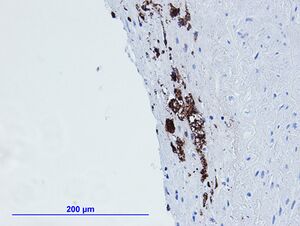

Immunohistochemistry determines protein expression profiles in tissues using chromagenic substrate (3,3′-Diaminobenzidine (DAB), benzene derivative). Primary antibody binds to the protein in tissue following with a conjugated peroxidase enzyme. Addition of hydrogen peroxide + DAB, catalyzes DAB to its oxidized, brown precipitate form.

- Primary antibody bound tissue protein + peroxidase (Horseradish peroxidase (HRP) 40kDa) conjugated secondary antibody (or biotin linked secondary antibody + avidin-HRP). In the presence of hydrogen peroxide (H2O2 (oxidizing agent)),HRP dependent DAB oxidation yields a brown precipitate. Therefore protein localization is measurable using DAB as a substrate.

- DAB is water soluble in an unoxidized form / forms water-insoluble brown precipitate under oxidation (H2O2 + HRP).

- HRP and H2O2 form a complex in the presence of DAB; HRP catalyzes breakdown of H2O2 (oxidizing agent) into water (H2O) and oxygen (O2). DAB is oxidized during this process while providing an electron source to drive the reaction.

- HRP forms a complex with hydrogen peroxide and yields water and oxygen. Free oxygen reacts with DAB to generate brown precipitate.